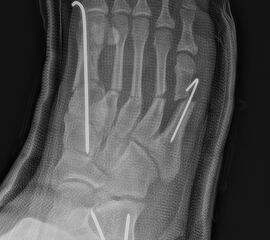

Zusätzlich schränken Wachstumsfugen die Wahl der Osteosynthese ein. Eine die Fuge kreuzende Osteosynthese ist ausschließlich mit Kirschner-Drähten möglich (Abb. 3).

Abb. 3 a-j: Beispiel einer Calcaneusverschiebeosteotomie mit offenen Wachstumsfugen und der entsprechenden Osteosynthese mit Kirschner Drähten. Lokalisation der Osteotomie (a), Lage der Fräse (b-d), Drahtlage mehrere Ansichten (e-h), Heilung der Osteotomie 4 Wochen postoperativ und Entfernung der Drähte (i-j).

Zum Lesen der Bildbeschreibung und zur Vollansicht bitte die Bilder anklicken. Bilder: A. Helmers.

Wachstumsfugen können, wie bereits oben in der generellen Einschätzung des Verfahrens für Kinder und Jugendliche erwähnt, durch direkte Manipulation mit einer Fräse oder indirekt thermisch geschädigt werden. Eine Osteosynthese, die offene Wachstumsfugen kreuzt, ist ausschließlich mit Kirschner-Drähten oder alternativ durch externe Tapezügel möglich. Implantierte Kirschner-Drähte können ohne eine weitere Narkose im Rahmen der Sprechstunde bei verheilter Osteotomie gezogen werden. Die Anwendung von externen Tapezügeln zur Stabilisierung von minimalinvasiven Osteotomien kann bei Kindern ohne Einschränkung durchgeführt werden (siehe Abb. 4 und Abb. 12). Bei sehr jungen Kindern sollten die Tapezügel allerdings nicht zu häufig gewechselt werden, da jeder Verbands- und Tapewechsel Stress für sie bedeutet.